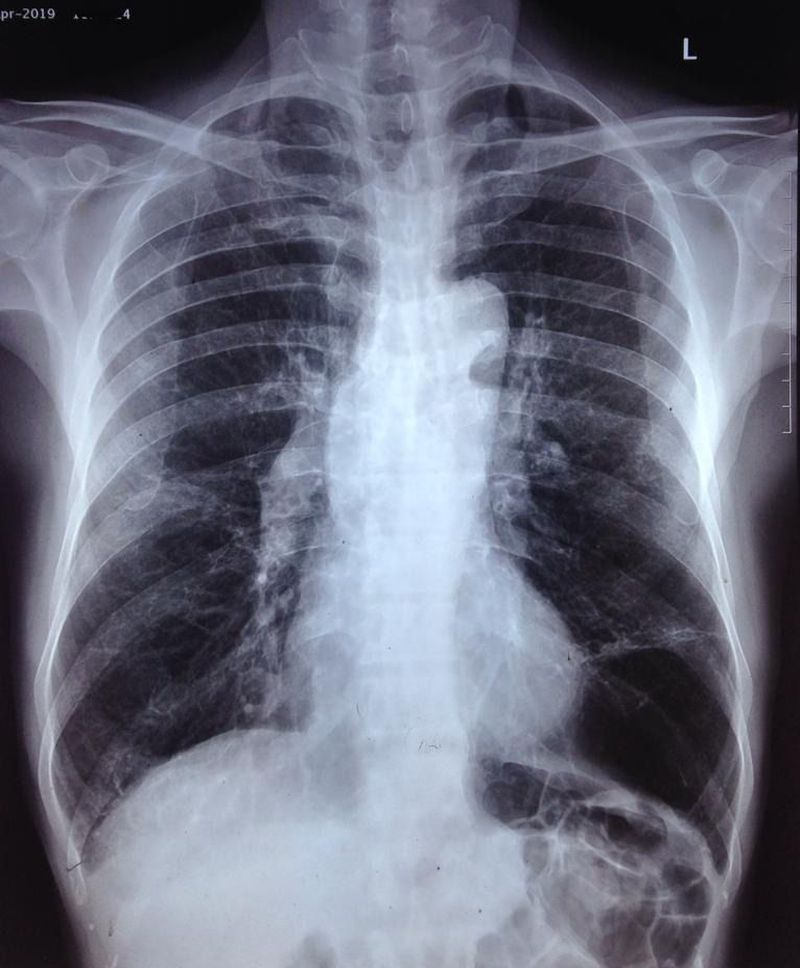

Seeing something 👨🏻‍⚕️👨🏻‍⚕️?

Left lower lobe something?? left horizontl fissure

Pneumothorax

Pneumothorax in left lower lobe

Barrel chest with Emphysematous bullae in left lower lobe